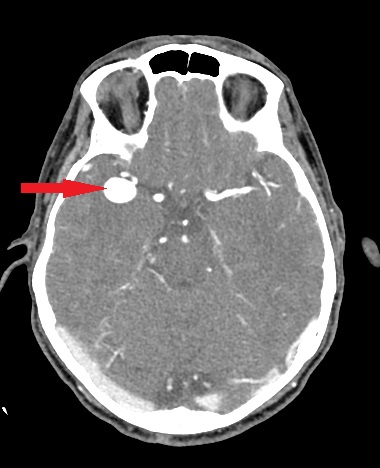

- Zmiany naczyniowe (np. naczyniaki jamiste, tętniaki)